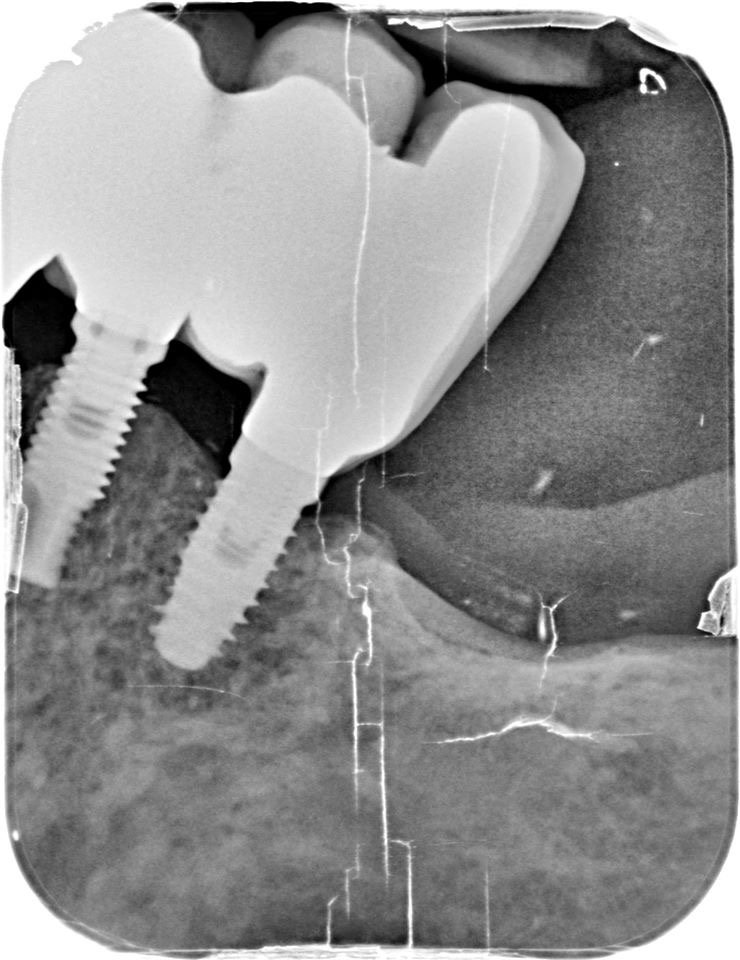

La paciente lleva implantes colocados hace más de 10 años con puentes cementados. En estos momentos el puente superior derecho ya no es posible cementarlo más y dado el estado [...]

Hola podríais ayudarme? La paciente coloco el implante de la pieza 36 en unidental .Quiere cambiar coronas.El implante 3.5 lo coloco en otro sitio pero al ser de conexión externa [...]

Buenas noches: Tenemos que rehabilitar estos 3 implantes colocados hace más de 15 años. Os detalle lo que sabemos de ellos: tiene un cono externo muy alto, redondo. el [...]